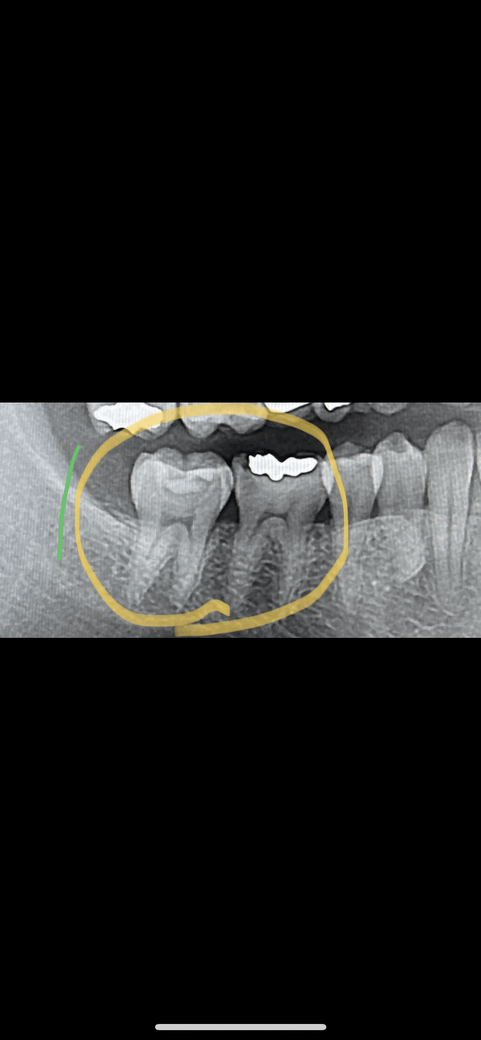

저xray는 작년 4월 사진입니다

사진을 보면 46번에 충치가 생겻지만

통증은 47번에 잇어서 47번을 신경치료 하엿습니다

근데도 지속적인 통증으로 46번 신경치료 하엿습니다

엑스레이상 외관상 깨긋하고 염증도 없엇지만

지속적인 자발통 에 의해저번달에 발치하엿습니다(46번)

엑스레이 찍고 외관상 바도 아무 문제 업답니다

47번도 현재 사진상 염증이 안보인다면, 현재의 극심한 자발통의 원인이 치아자체에 있기보다는, 근육에 의한 연관통의 가능성도 잇어보입니다.